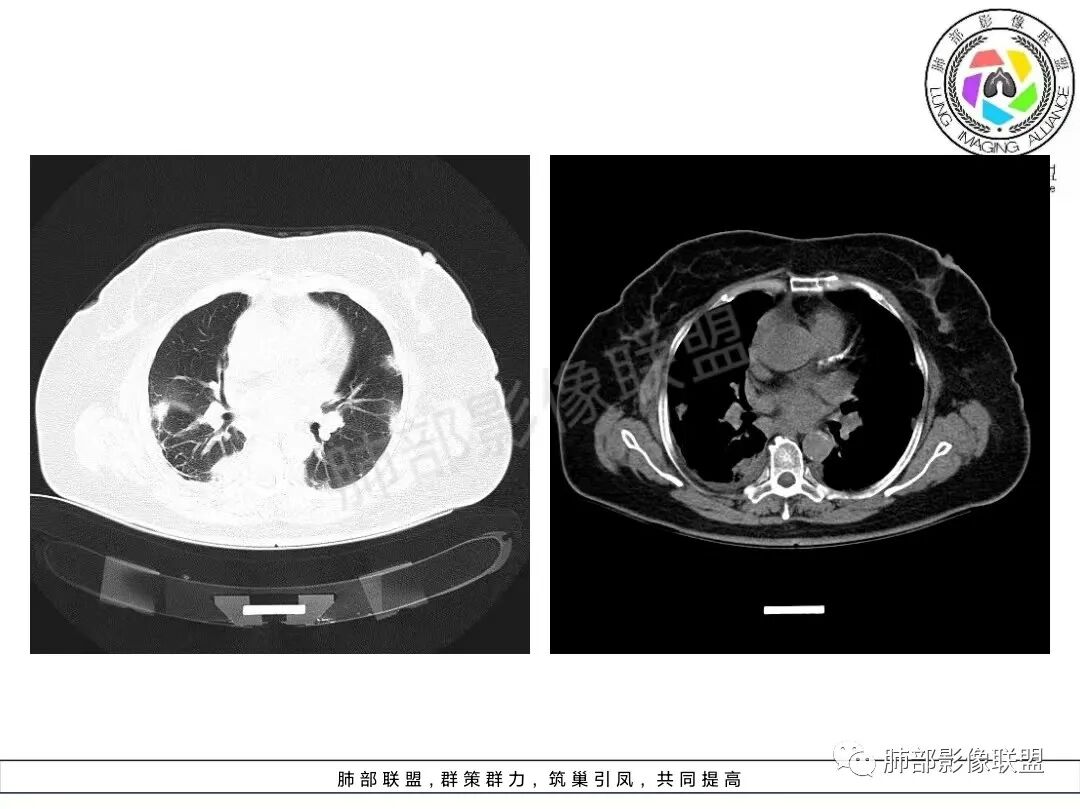

两肺沿胸膜下分布为主,大片、斑片状不均质实变,肺窗>纵隔窗,提示累及肺实质和间质,实变内充气支气管征空洞几乎不见,边缘收缩凹陷,部分平直,肺体积整体未见缩小。临床血氧降低,白细胞升高,考虑OP,COP,鉴别隐球菌,粘液腺癌!

老年女性,咳嗽、咳黄白痰,无发热,化验炎性指标高,右肺胸膜下实变,其内支气管充气、扩张,周围索条,左肺胸膜下多发结节及斑片实变,胸膜下线影,右侧少量胸水,考虑机化性肺炎,鉴别隐球菌、粘液腺癌

双肺胸膜下多发实变,边界不清,较大病变长轴与胸膜平行,近端可见充气支气管征,部分病灶内坏死边界清,胸膜下有多发相类似病灶,综合考虑首选隐球菌,其次0P尚不除外

双肺胸膜下多发斑片及大片实变影,边缘清晰,长轴平行于胸膜,部分病灶呈细网格状,右侧胸膜增厚,右侧叶间胸膜增厚,血糖高,感染指标高,考虑OP,鉴别隐球菌

双肺胸膜下大片、斑片影,密度不均,边缘模糊,周围索条,右侧少量胸水,考虑机化性肺炎,鉴别隐球菌、粘液腺癌

2、影像特点:双肺胸膜下为主、多发斑片影、结节样实变影及磨玻璃样密度影,大部分病灶边缘平直、边界清,磨玻璃密度病灶内可见细网格影,部分病灶内可见支气管扩张表现,部分支气管直达远端,部分中断于病灶中部。部分病灶有侧向融合趋势。